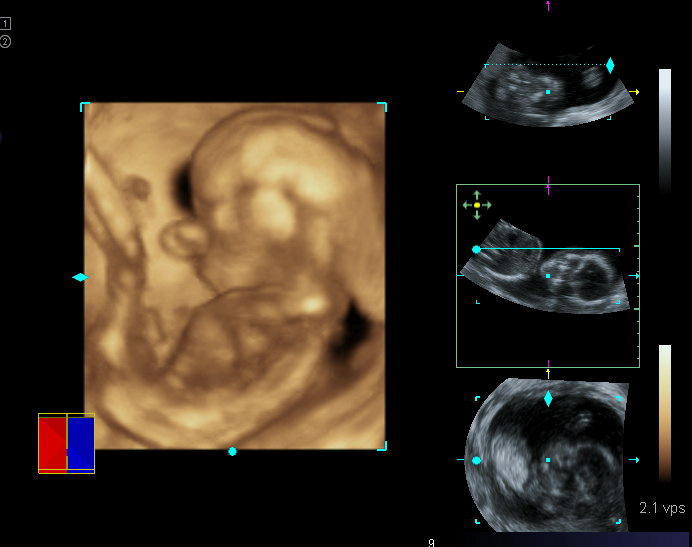

On Monday, January 17, we went for our week 20 ultrasound. The ultrasound tech took lots of measurements and determined that Baby G was measuring at 20 weeks and 5 days (instead of the 20 weeks and 1 day calculated from our due date). They don't usually adjust the due date, but we will definitely keep that information in mind! Everything looked good and at the very end (after much suspense) she told us that Baby G is a boy! Now we can begin the nursery planning; we're still thinking of keeping the colors gender neutral (I'm rooting for yellow). We have also begun the name search. We are going to keep the name secret once we do pick one.